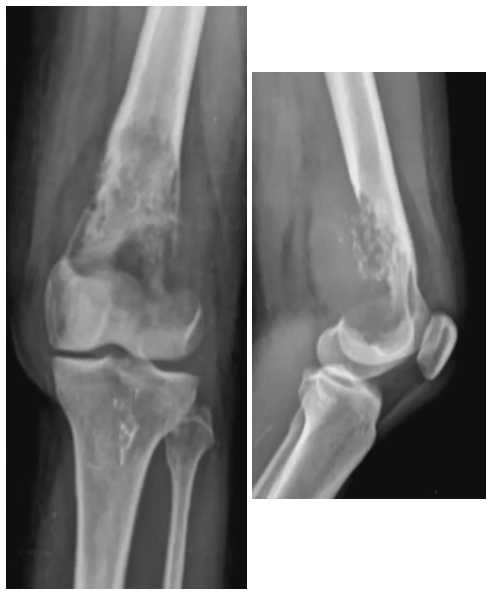

# Princípios básicos de tumores ósseos - Com base na imagem, classifique de acordo com Enneking:

- **B3 → agressivo** (*rompe a cortical*)

# Princípios básicos de tumores ósseos - De acordo com a imagens e as características listadas abaixo, classifique de acordo com Enneking: - Tumor maligno - Baixo grau - Sem metástase

- Baixo grau → **I** - Extracompartimental (extensão para partes moles visto na radiografia) → **B** - Classificação de Enneking → **I B**

# Princípios básicos de tumores ósseos - De acordo com a imagens e as características listadas abaixo, classifique de acordo com Enneking: - Tumor maligno - Osteossarcoma clássico de alto grau na biópsia - Sem metástase

- Alto grau → **II** - Extracompartimental (extensão para partes moles visto na radiografia) → **B** - Classificação de Enneking → **II B**